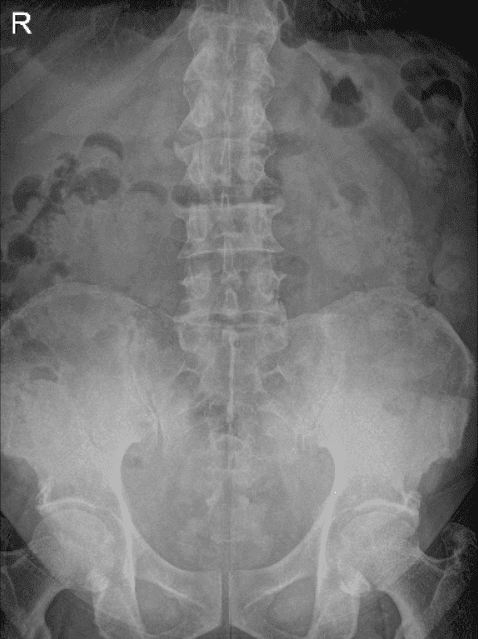

A 63-year-old patient was in our office with complaints regarding pain in his knees which was severe, and he felt that something was broken. He described the pain as sharp. He stated that his right hand and lumbar spine are mild in nature. T

he biggest problem is his knees he feels clicking and popping. He had some arthritis in the right knee before the accident, but it was all right after a steroid injection. The pain in the right knee is worsened, severe and different from the one before.

He presented X Ray of his bilateral knees, lumbar spine, and right hand from Zwanger. His Xray results showed mild osteoarthritic degenerative changes. There are no fractures. For his lumbar spine mild multilevel lumbar degenerative changes. For his right hand, normal right hand.

Left and Right knee X-ray complete with patella

LS Spine X-ray Flex/Ext no obliques